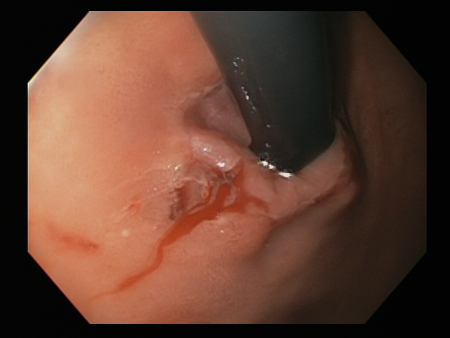

A chronic cough may be associated with whooping cough, bronchitis, bronchiectasis, emphysema, chronic obstructive pulmonary disease, or lung cancer.[25][Figure caption and citation for the preceding image starts]: Bleeding Mallory Weiss Tear viewed on retroflexionFrom the personal collection of Douglas Adler; used with permission [Citation ends].

[Figure caption and citation for the preceding image starts]: Bleeding Mallory Weiss Tear viewed on retroflexionFrom the personal collection of Douglas Adler; used with permission [Citation ends].